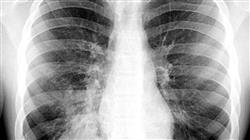

Le Infezioni Respiratorie colpiscono sia la popolazione infantile che quella adulta e sono diventate una delle principali cause di morte nell'ambito delle infezioni. I più frequenti sono le polmoniti e la tubercolosi.

In questo caso, il programma si concentra sulle Infezioni Respiratorie più letali, prendendo come base le polmonite batteriche, la tubercolosi, la sindrome di Loeffer e le sindromi eosinofile. Inoltre, fa conoscere quali sono gli antimicrobici più efficaci nel campo delle Infezioni Respiratorie.

Corso Universitario in Infezioni Respiratorie

Durante il corso, gli studenti saranno in grado di conoscere le principali infezioni del sistema respiratorio come il raffreddore comune, l'influenza, la polmonite, la bronchite e la tubercolosi, tra gli altri. Inoltre, saranno affrontate le cause e i fattori di rischio di queste malattie, nonché le misure di prevenzione e controllo che devono essere attuate per evitare la loro diffusione. TECH ha una metodologia pratica in cui i partecipanti troveranno letture specializzate, risorse multimediali e una libreria virtuale, nonché diversi strumenti ospitati sulla nostra piattaforma disponibile 24 ore al giorno, che fungono da complemento ideale agli incontri online con gli insegnanti specialisti. Al termine del corso, i partecipanti riceveranno un certificato universitario che attesterà la loro formazione nel campo delle infezioni respiratorie. Questo certificato permetterà loro di eccellere nel campo del lavoro e aprirà nuove opportunità di crescita professionale. Non perdere l'opportunità di specializzarti in questo importante campo della medicina. Iscriviti subito al nostro Corso Universitario in Infezioni Respiratorie e diventa un esperto nella diagnosi e nel trattamento di queste malattie. Ti stiamo aspettando!